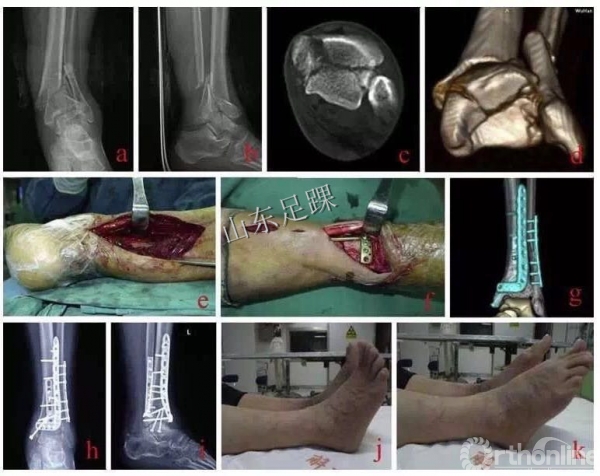

(2)一期:(恢复肢体长度和力线)跟骨牵引;外固定;腓骨骨折复位内固定、胫骨后踝骨折有限切开复位内固定;预防血栓。

(3)二期:约10—14天后,胫骨骨折切开复位内固定。

(4)二期手术的软组织条件为:手术部位的淤血吸收,骨折水疱处出现表皮再生,开放性骨折的伤口愈合且没有感染,软组织水肿消退且皮肤出现皱缩。

复位胫骨远端关节面时,需要辨认3个主要的骨折块:Volkmann骨块、Chaput骨块和内踝骨块。

关节面复位要由后向前、由外向内的顺序进行,后方的Volkmann骨块是复位的关键。